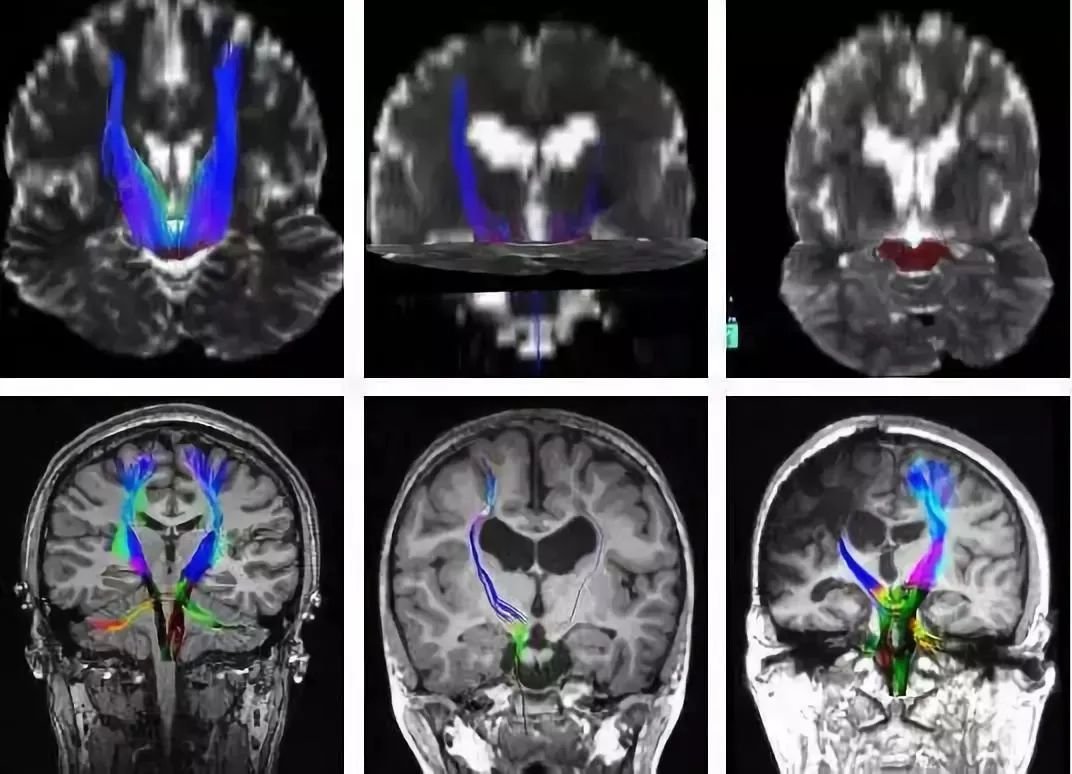

2. DTI:

扩散张量成像是一种专门的MRI,允许我们绘制半卵圆中心神经纤维的路径并研究这些路径的完整性。

▼DTI成像技术